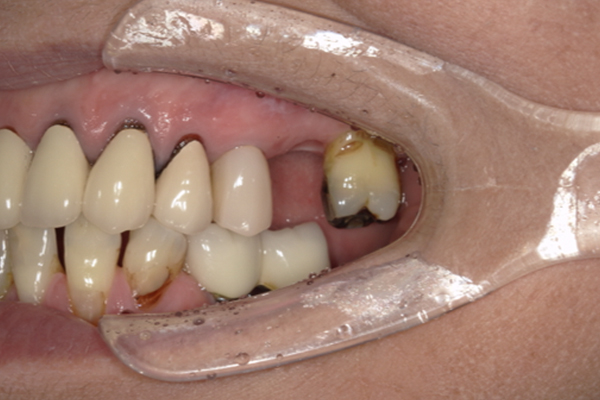

| 主訴 | 上の歯がぐらぐらする |

|---|---|

| 治療内容 | 上顎の歯が重度の歯周病のため全て抜歯し、

上顎に対するインプラント治療を行った。 午前中にインプラントの土台を入れ、夕方に上部構造(歯)を装着。 1日で噛めるようになる治療法。 |

| 治療期間 | 1日 |

| 治療費 | 250万円 |

| 治療 リスク | インプラント治療後2、3日はやや痛みを伴うことがあります。 |